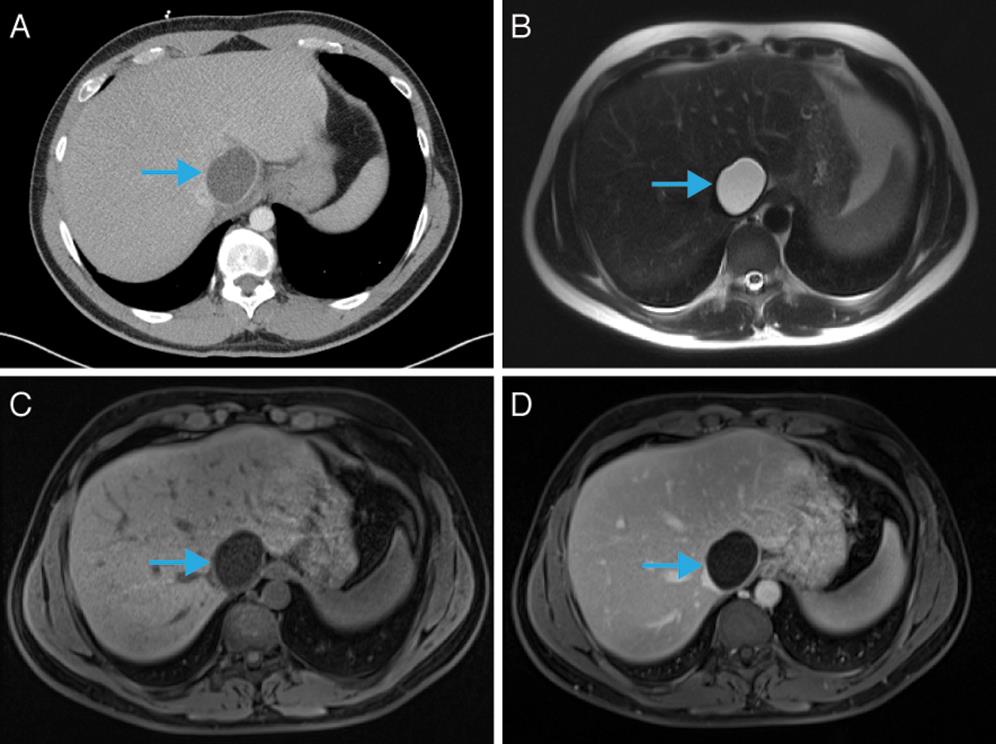

На Т1-взвешенных изображениях определяется образование округлой формы с чёткими контурами и гипоинтенсивным сигналом, соответствующим жидкостному содержимому эхинококковой кисты.

На Т2-взвешенных изображениях визуализируется киста с гиперинтенсивным однородным сигналом, а также выявляются множественные дочерние кисты с характерным «сотовым» паттерном в структуре основного образования.

В режиме с подавлением сигнала от жира определяется чёткая капсула эхинококковой кисты, окружённая участками гипоинтенсивного сигнала вследствие перифокального фиброза печени.

В режиме с подавлением сигнала от воды выявляется внутренняя перегородчатая структура кисты с гипоинтенсивными перегородками, которые отражают фиброзные изменения внутренней оболочки эхинококка.

В нативном режиме определяется округлое жидкостное образование с низкой плотностью и чёткими контурами, окружённое выраженной кальцинированной или фиброзной капсулой.

В режиме сканирования мягких тканей визуализируются чёткие перегородки и дочерние кисты в просвете основного образования, что придаёт типичный «сотовый» вид кисте.

В режиме с контрастированием определяется усиление стенок и перегородок без накопления контраста жидкостным содержимым, что подтверждает паразитарную природу кисты.